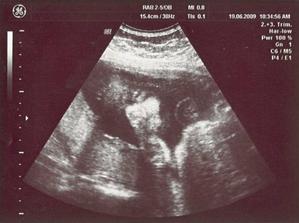

7/5 09 genet. utz - tak už víme na 100% že čekáme Marianku, všechno je v pohodě, je zdravá ... Máju jsme si nechali nahrát na DVD z 2D utz

28/5 09 PORADNA 23 + 4 tt - placenta je ok, doufám že už to tak zůstane ... Mája se zase na utz předváděla, podle dr. máme dost akční dítě, tak snad jí ta hyperaktivita opustí než se narodí 🙂) ... máme další fotku, jak jinak 🙂)